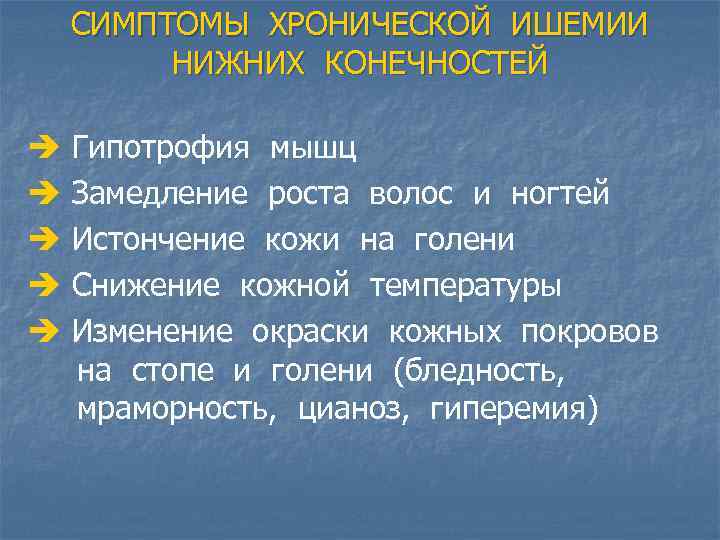

СИМПТОМЫ ХРОНИЧЕСКОЙ ИШЕМИИ НИЖНИХ КОНЕЧНОСТЕЙ è è è Гипотрофия мышц Замедление роста волос и ногтей Истончение кожи на голени Снижение кожной температуры Изменение окраски кожных покровов на стопе и голени (бледность, мраморность, цианоз, гиперемия)